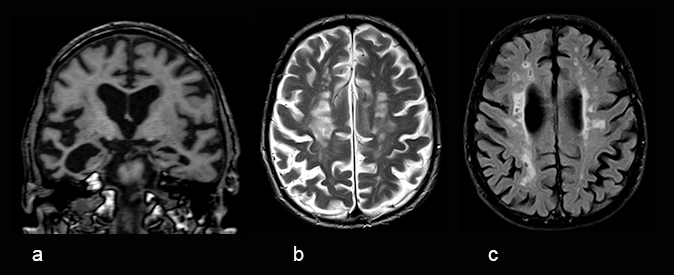

Muistipotilaan rutiinikuvausprotokolla magneettikuvauksessa (Muisti-MK)

Muistihäiriöpotilaan rutiinikuvausprotokollaan kuuluvat MK:ssa vähintään T1-painotteinen 3-dimensionaalinen kuvasarja (a) sekä transaksiaalinen T2-painotteinen (b) ja Flair-sarja (c). On suositeltavaa kuvata rutiinisti myös hemosideriinille herkkä SWI- tai T2*-sekvenssi ja diffuusiokuvaus. Tarvittaessa kuvataan myös lisäsekvenssejä, kuten varjoainetehosteinen sarja.